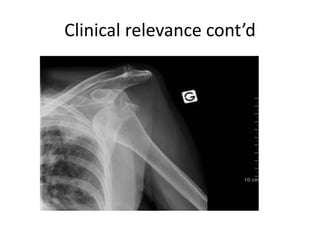

CLINICAL RELEVANCE

1. Dislocation of the Shoulder Joint

• Clinically, dislocations at the shoulder are described by where the

humeral head lies in relation to the glenoid fossa. Anterior dislocations

are the most prevalent (95%), posterior (4%) and inferior (1%)

dislocations can sometimes occur. Superior displacement of the

humeral head is prevented by the coraco-acromial arch.

• An anterior dislocation is caused by excessive extension and lateral

rotation of the humerus. The humeral head is forced anteriorly and

inferiorly – into the weakest part of the joint capsule. Tearing of the

joint capsule is associated with an increased risk of future dislocations.

Hill-Sachs lesions (impaction fracture of posterolateral humeral head

against anteroinferior glenoid) and Bankart lesions (detachment of

antero-inferior labrum with or without an avulsion fracture) can also

occur following anterior dislocation.